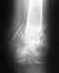

в марте была травма наружного мыщелка: перелом в коленном суставе без смещения осколков в связи с чем проводится в данный момент традиционное лечение: 1 месяц - лангетка, со второго месяца - тутор Передвижение на костылях, полный покой ноги.После травмы до сих пор не проходит полностью отек в следствии чего назанчены препараты - антистакс и нимесил, Подскажите насколько продуктивно данное лечение какие еще могут быть эффективные методы лечения при данной травме и по срокам - сколько в фиксированном положении и как долго нельзя ступать на ногу..Какие могут быть последствия и как их избежать

Без снимков определенное что-то не сказать ни про повреждение, ни про соответствие ему лечения. Так, абстрактно, можно только упомянуть, что отек при переломе может быть в течение нескольких месяцев.